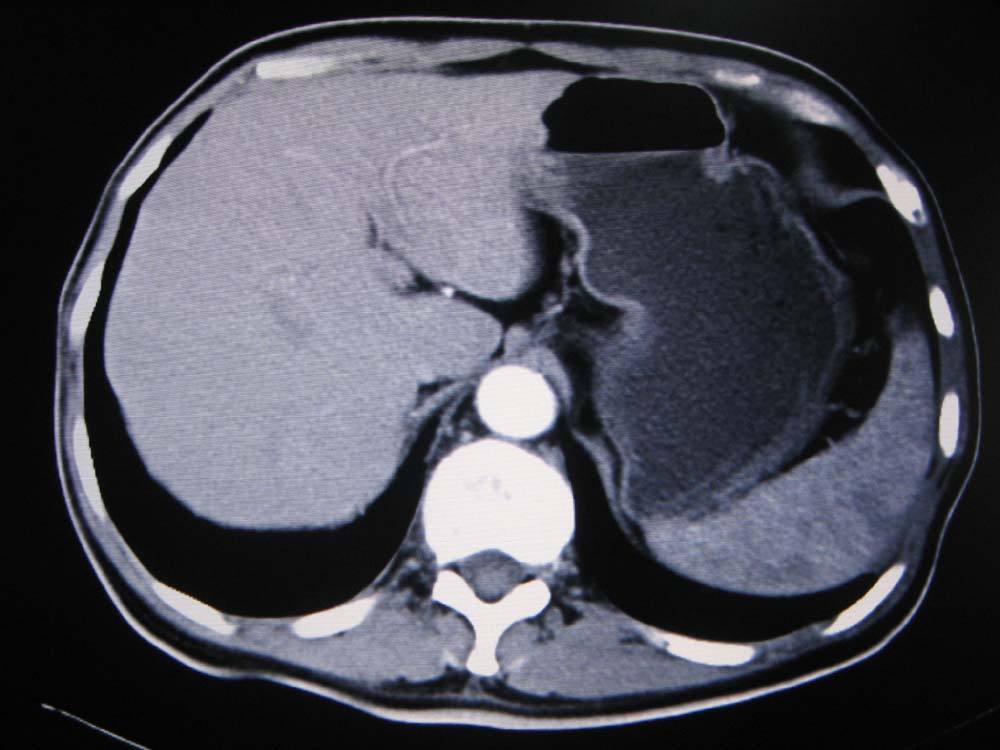

这是一张腹部的CT检查图片。

临床上CT检查最常显示的是人体横断面(相当于上一部分的下断面),在这个断面上可以看到结构的哪些方位?